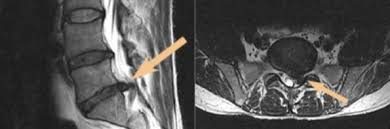

Bandscheibenprotrusion l4/5. They are relatively easy to overlook as they do not impinge upon the spinal canal. Die Bandscheibenprotrusion der LWS beschreibt nun den Zustand in dem sich einer der Kerne einer Bandscheibe nach hinten vorgewölbt hat und auf Teile des Rückenmarks oder zentrale Nerven drückt. Die Symptome ähneln dann denen eines Bandscheibenvorfalls.

They do not narrow the subarticular recess but compresses the exiting nerve root only thus clinically mimicking a posterolateral disc from the level aboveAs posterolateral discs are common as is multilevel. Computertomographisch zeigten sich ein Vakuumphänomen und eine Bandscheibenprotrusion mit Forameneinengung rechts L45 bei. Die Bandscheibenprotrusion auch Bandscheibenvorwölbung oder inkompletter Bandscheibenprolaps ist eine mit dem Alter zunehmend häufiger zu beobachtende Veränderung im Bereich der Wirbelsäule.

These levels were investigated in this study as degeneration occurs most often and earliest in these three lower vertebral levels 17 fourth and fifth lumbar spine vertebrae and the first sacral vertebra were evaluated for disc bulging and protrusion See Lumbar Artificial Disc Replacement for Chronic Back Pain A high intensity zone HIZ is seen at L4-L5 Depending on the extensiveness. Es wurde eine ausgeprägte Osteochondrose mit Pseudolisthese und Bandscheibenprotrusion L45 diagnostiziert. Bei einer Bandscheibenprotrusion können die Nervenwurzeln hier blau geschädigt werden.

Im Gegensatz zum Bandscheibenvorfall bei dem der äußere Faserring der Bandscheibe zumindest teilweise gerissen und der Kern relativ weit nach hinten gerutscht ist ist bei der Bandscheibenprotrusion.

Die Schmerzsymptomatik wird durch die Vorwölbung ausgelöst die gegen einzelne Nerven Nervenbündel Nervenwurzeln oder auf das Rückenmark drücken kann. Die Schmerzsymptomatik wird durch die Vorwölbung ausgelöst die gegen einzelne Nerven Nervenbündel Nervenwurzeln oder auf das Rückenmark drücken kann. Eine Bandscheibenvorwölbung nennt man in der medizinischen Fachsprache Bandscheibenprotrusion - dabei wölbt sich der Faserring der Bandscheibe in Richtung des Nervenkanals vor. Bei dieser Erkrankung der Wirbelsäule rutscht der innere gallertartige Kern Nucleus pulposus aus seiner ursprünglichen Position. Sie kann so zum Beispiel zu den typischen Rückenschmerzen bei einem Hexenschuss führen. Wenn der Gallertkern fast bis zum äußersten Bereich des Faserrings vordringt der bis zum Außenumfang des Wirbelkörpers vorsteht ohne das hintere Band zu dehnen. Die Bandscheibenprotrusion ruft daher wenn überhaupt meist nur Wirbelsäulensymptome hervor. Computertomographisch zeigten sich ein Vakuumphänomen und eine Bandscheibenprotrusion mit Forameneinengung rechts L45 bei. Welches mögliche Symptome sind erfahren Sie in diesem Ratgeber.

Wenn der Gallertkern fast bis zum äußersten Bereich des Faserrings vordringt der bis zum Außenumfang des Wirbelkörpers vorsteht ohne das hintere Band zu dehnen. Die Bandscheibenprotrusion der LWS beschreibt nun den Zustand in dem sich einer der Kerne einer Bandscheibe nach hinten vorgewölbt hat und auf Teile des Rückenmarks oder zentrale Nerven drückt. Diese unterscheidet sich vom Bandscheibenprolaps im. Der dritte Grad erzeugt Lombalgie Kreuzschmerzen und Ischialgie. Die Bandscheibenprotrusion auch Bandscheibenvorwölbung oder inkompletter Bandscheibenprolaps ist eine mit dem Alter zunehmend häufiger zu beobachtende Veränderung im Bereich der Wirbelsäule. Die Symptome ähneln dann denen eines Bandscheibenvorfalls. Je nach Lage der Vorwölbung und der betroffenen Bandscheibe haben Menschen mit Bandscheibenprotrusion überhaupt keine Beschwerden die Schmerzen treten örtlich begrenzt.